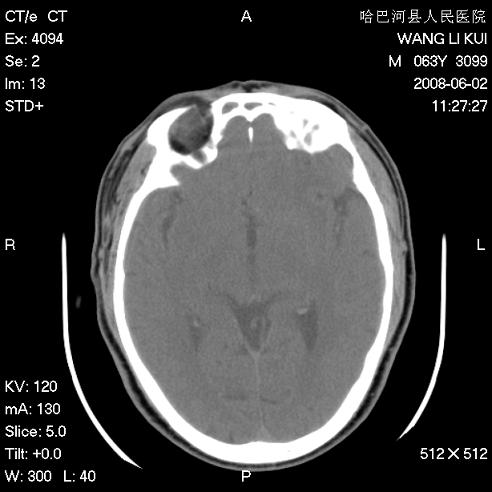

标题: CT13803:反复性鼻塞、流涕一年余 [打印本页]

标题: CT13803:反复性鼻塞、流涕一年余

副鼻窦炎,右上额窦积脓。左眼肌锥内见致密影,视神經受压

全组副鼻窦炎 肌锥内高密度灶。建议进一步检察检查

2、左眼眶肌锥内病变,小血管瘤?建议增强。

2、左眼眶肌锥内病变,建议增强

1)全副鼻窦炎(左侧上颌窦黏膜下囊肿或息肉)。2)左眼眶肌锥内不规则小结节状软组织密度影;考虑为小血管瘤可能。建议行ct增强扫描检查。

全组副鼻窦炎,左侧肌锥内不规则形软组织肿块影,与眼外肌密度相当,左侧视神经受压,肿块与视神经及眼外肌分界清晰,眼外肌无增粗,眶壁无破坏,球后脂肪间隙不模糊,考虑良性改变,小血管瘤或神经源性肿瘤可能,建议增强扫描。

谢谢,增强扫描做了,眶内病灶与海绵窦同步明显强化,血管瘤